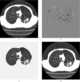

Mucoid impaction in bronchus